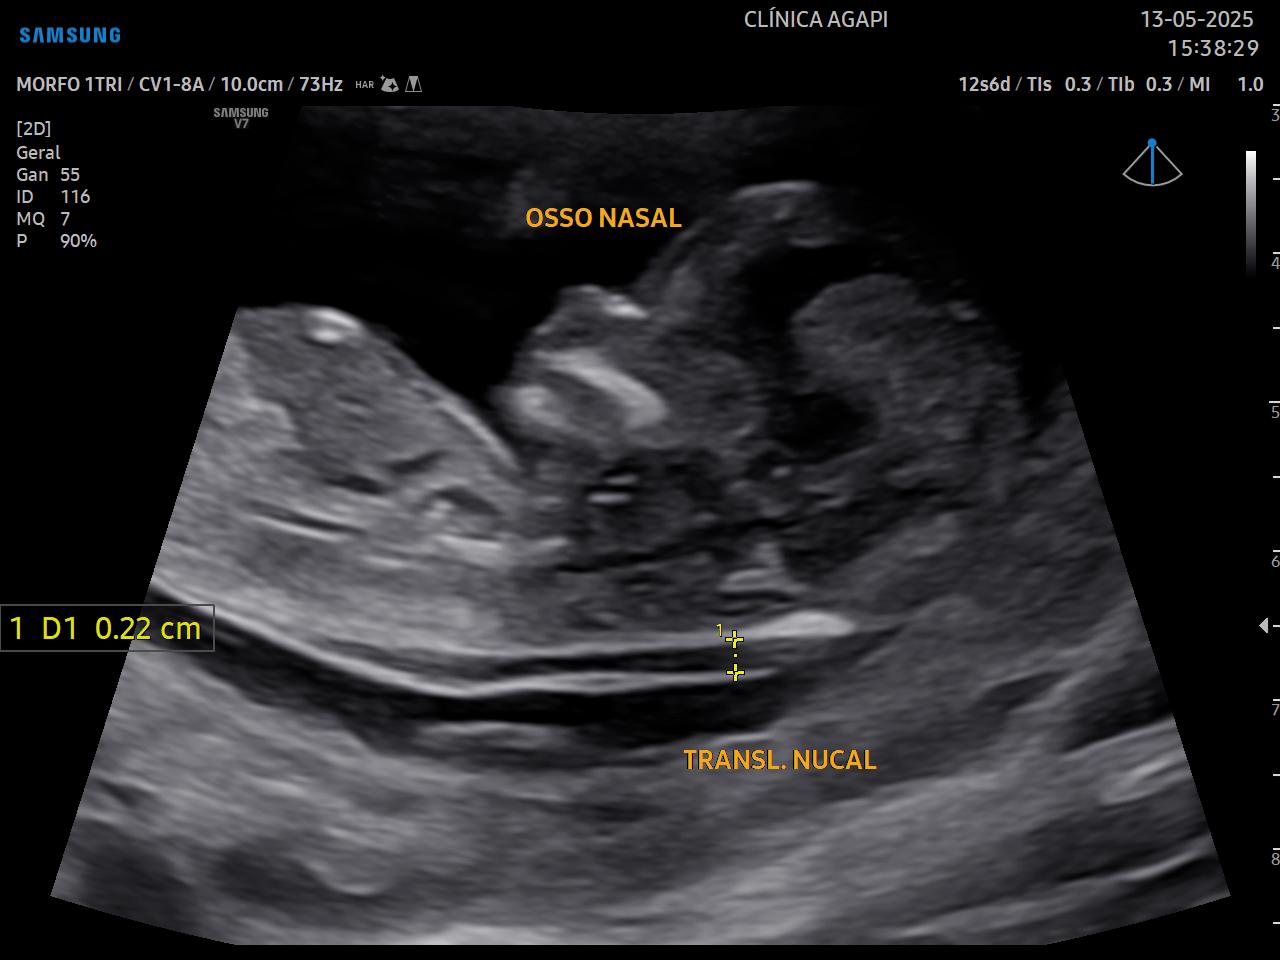

O rastreio de aneuploidias é feito através da avaliação de marcadores ultrassonográficos específicos como: transluscência nucal, osso nasal, ducto venoso e regurgitação tricúspide.

Na AGAPI realizamos o exame completo, incluindo os cálculos de risco de alterações cromossômicas e de pré-eclâmpsia, conforme algoritmo da Fetal Medicine Fundation (https://fetalmedicine.org).